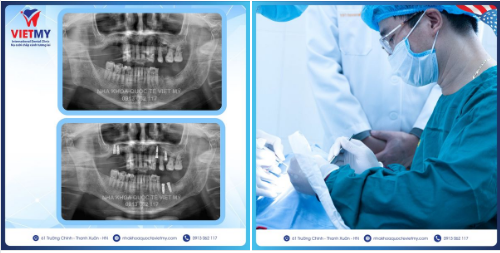

Case trồng răng Implant cho cô Nhung đến từ Long Biên- Hà Nội

Tình trạng: Mất R15-> R17, R24, R26, R36, R37

Thực hiện: Cấy ghép Implant R16, R17, R24, R26, R36, R37

Được thực hiện bởi bác sỹ Lê Thiên Quế_ Chuyên gia hàng đầu trong lĩnh vực trồng răng implant với hơn 20 năm kinh nghiệm, công nghệ hiện đại phòng cấy ghép vô trùng khép kín 100% an toàn tuyệt đối